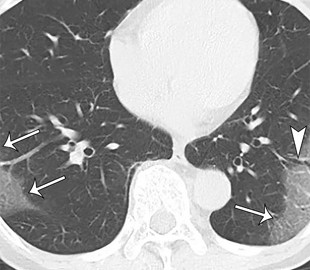

Специалисты компании «Платформа Третье мнение» разработали алгоритмы машинного обучения, благодаря которым компьютер может в 50 раз быстрее, чем человек, находить признаки коронавирусной инфекции по компьютерной томографии (КТ).

Как пишет издание «Ведомости», анализ снимка КТ в среднем занимает до десяти минут у врача. Алгоритмы же могут сделать это за 12 секунд.

Сообщается, что система диагностики на технологии компьютерного зрения прошла испытания и будет тестироваться в поликлиниках и стационарах Москвы.

Специалисты уточнили, что компьютер не заменит специалиста-радиолога, он лишь расширит его возможности. В конце концов ответственность за постановку диагноза всегда будет лежать на враче.